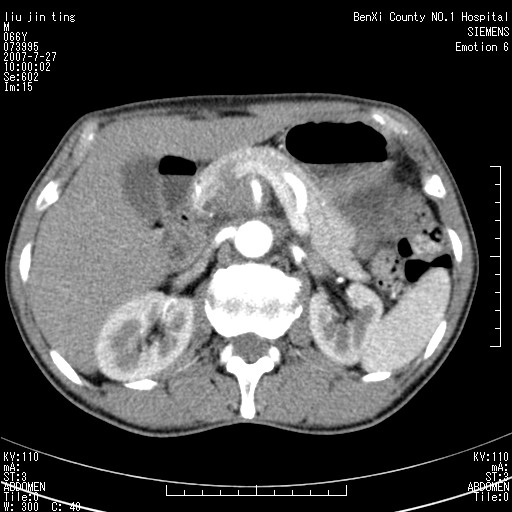

腹痛,背痛,无恶心呕吐,不黄,彩超示胰腺钩癌,ct扫描病灶平扫30-40hu,增强后动脉期40--60hu,静脉期50-68hu,真的是钩突上的么?您要试一试么?

动脉期

静脉期

沿着肠系膜上动脉呈匍匐性生长的软组织肿块,形态不规则,包绕肠系膜上动脉,呈明显强化,考虑来源于肠系膜的恶性肿瘤

沿着肠系膜上动脉呈匍匐性生长的软组织肿块,形态不规则,包绕肠系膜上动脉,呈轻-中度强化,考虑来源于肠系膜的恶性肿瘤。

钩突是正常的,只见腹膜后淋巴结的肿大,考虑淋巴瘤或转移可能。